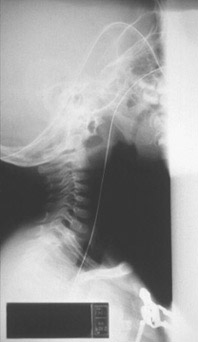

Lateral neck film of a 1 year old child in acute respiratory distress.